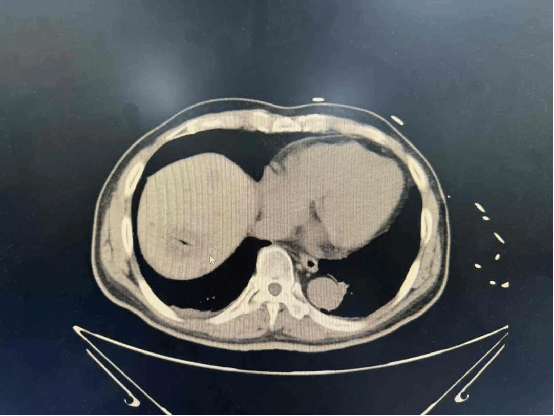

2025-11-10“小创伤 大作用”,肿瘤内科开展肝恶性肿瘤微波消融术

经皮肝微波消融术,是现代医学“微创、精准、高效”理念的杰出代表。它用“一根针”的技术,实现了“精准消灭癌细胞”的战略目标,为无数肝癌患者带来了新的希望和选择... -